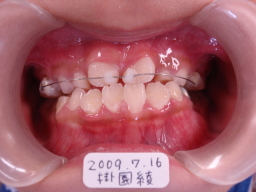

| 2009年07月16日(7才5ヶ月) 第一大臼歯がはえてこない(固定源がない)ので、 リンガルアーチが入れれない。 従って上顎切歯を前方に出すため、乳臼歯(DE)と 上顎切歯にワイヤーを接着剤で上顎切歯を前方に 移動させるように装着 |

|

| 上顎切歯の被害が改善(反対咬合が治った)状態で、ワイヤーをはずす。 ↓その約2年5ヶ月後 |